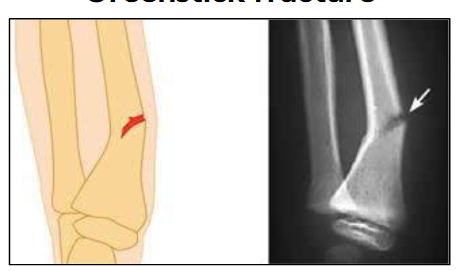

What type of fracture is this?

Greenstick fracture

Prone in young children